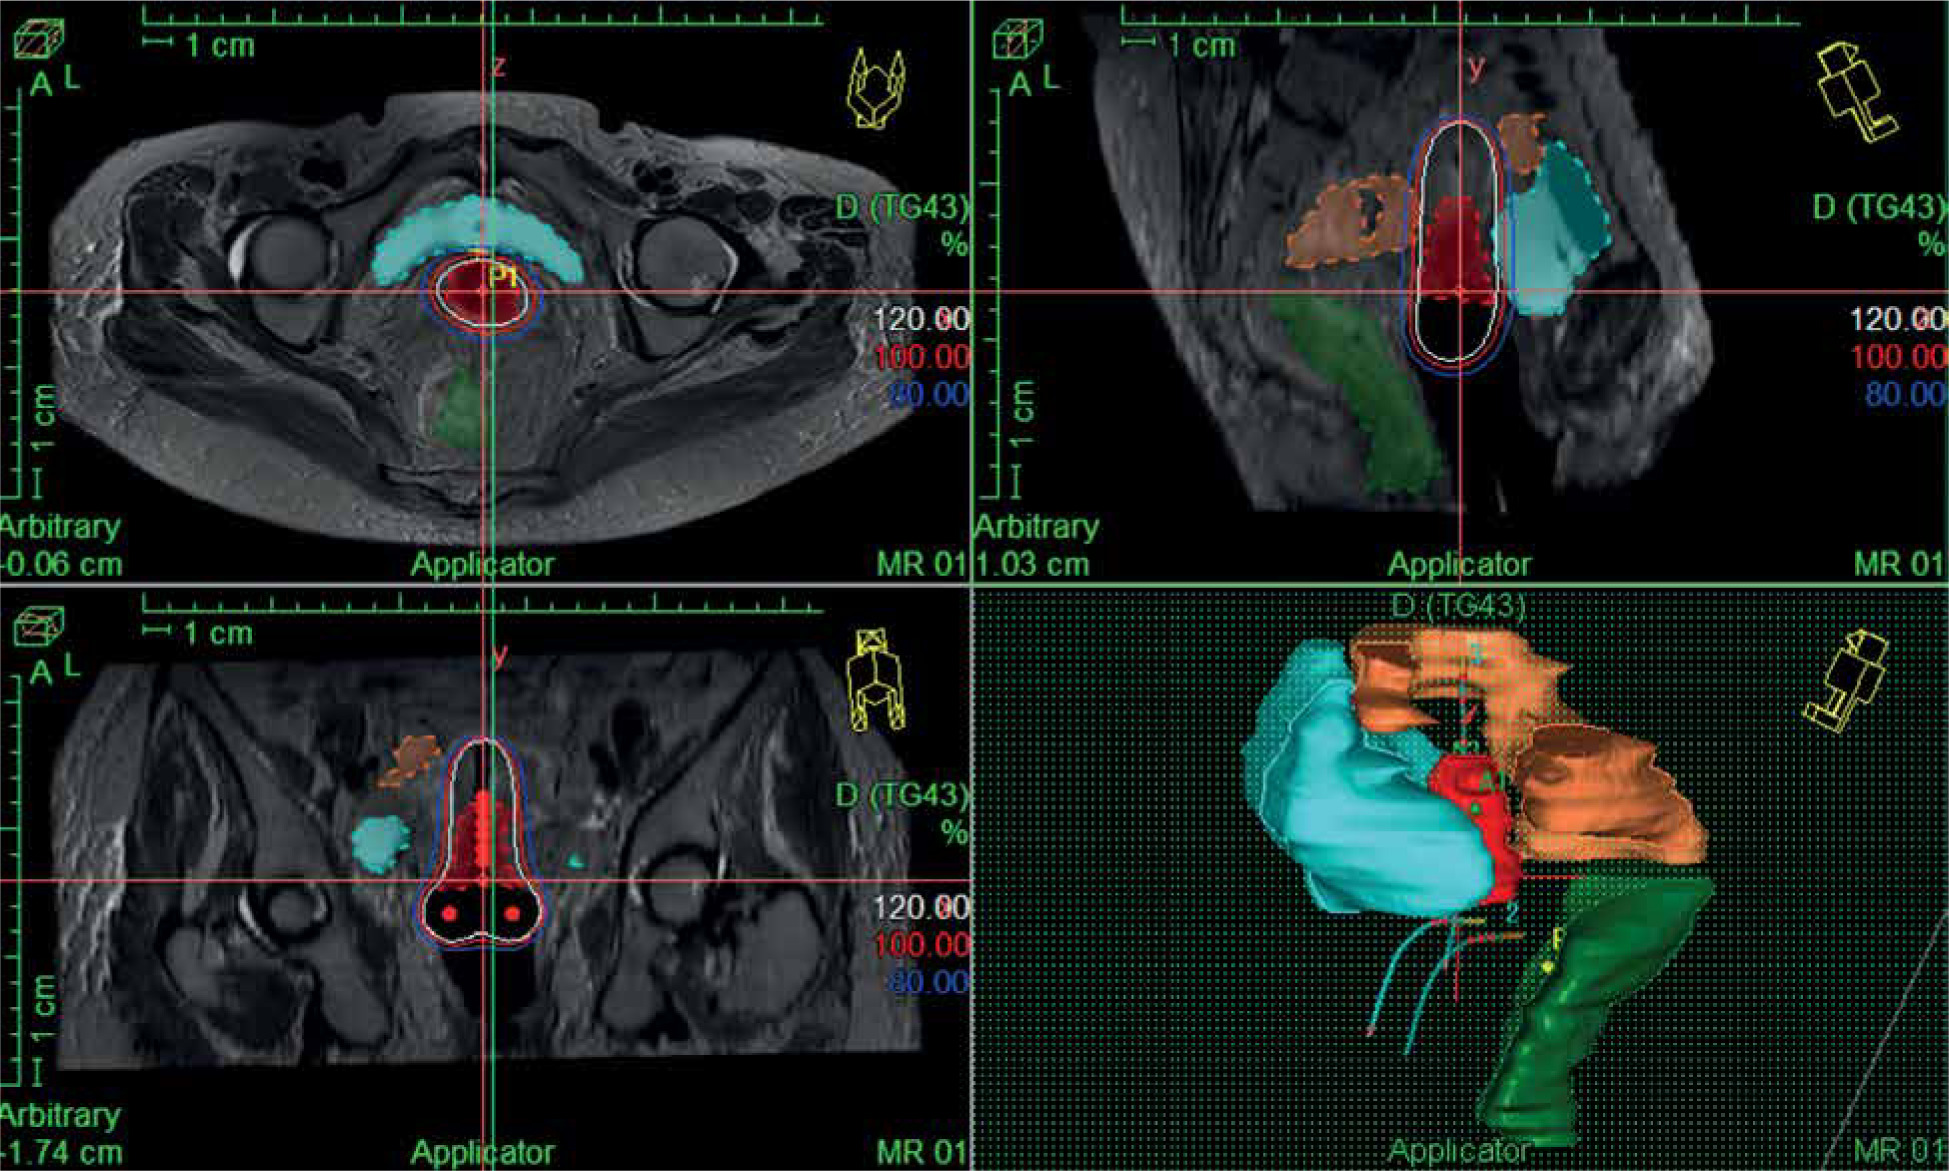

Imaging and planning of IGBT

In the first fraction of IGBT, T2-weighted sequences in para-axial, para-sagittal, and para-coronal planes were obtained on 3T MRI (GE Healthcare) with a pelvic coil, which were used for IGBT planning during the first session. Subsequent three BT sessions were done under CT guidance using CT scanner (Siemens Somatom Sensation Open). MRI/CT images were acquired without intravenous contrast at 3 mm slice thickness covering an anatomical region extending from the L4-L5 vertebrae to the ischial tuberosity. Then, the MR/CT images were imported into Oncentra TPS version 4.5.3 (Nucletron, an Elekta company, Elekta AB, Stockholm, Sweden). Delineation of HR-CTV during first fraction was performed according to GEC-ESTRO recommendations [17, 18]. Delineation of HR-CTV was based on MRI information at the time of first fraction supported by clinical examination findings. HR-CTV volume included the entire cervix, gross disease at the time of IGBT, and grey zones on MRI. HR-CTV was delineated on CT images for subsequent fractions (CT1, CT2, CT3) according to Viswanathan et al. guidelines [26]. HR-CTV delineation on CT was based on clinical examination at the time of brachytherapy as well as information from MRI done at the first fraction of IGBT. Volumes and dimensions of HR-CTV were noted at each fraction of IGBT. Prescribed dose was 7 Gy × 4 fractions to HR-CTV (volume-based plan) for all patients (Figure 2), and DVHs for HR-CTV and OARs were evaluated. D90 (minimum dose covering 90% of target volume) of HR-CTV was recorded for all patients. D2cc (minimum doses calculated at the most irradiated 2 cc volumes) of the bladder, rectum, and sigmoid colon were assessed. The total reference air-kerma (TRAK) values and point-A doses for each fraction were also documented. Cumulative doses to HR-CTV and OARs (WP-IMRT and IGBT) were converted to equivalent doses in 2 Gy per fraction (EQD2) using linear-quadratic model (with α/β value of 10 for tumor, and α/β value of 3 for OARs) [27].

EQD2 of WP-IMRT and IGBT were summed up to evaluate the volume-based plan with regards to DVH constraints corresponding to a prescribed EQD2 dose of at least 80 Gy α/β 10 (D98% of WP-IMRT plus D90% of IGBT). For OARs, cumulative total EQD2 dose (D2% of WP-IMRT plus D2cc of IGBT) were aimed to be ≤ 65 Gy α/β 3 for the rectum, ≤ 70 Gy α/β 3 for the sigmoid, and ≤ 80 Gy α/β 3 for the bladder, respectively. IGBT treatment was delivered with iridium-192 source (MicroSelectron HDR, Nucletron, an Elekta company, Elekta AB, Stockholm, Sweden). After completion of the treatment, applicators were removed, and routine antibiotics and symptomatic medications were advised to avoid infections and patients’ discomfort.

Table 3 shows the comparison of HR-CTV doses, dimension, volumes, point-A doses, and TRAK for different fractions of IGBT. The median per fraction doses of IGBT for D2cc bladder, D2cc rectum, and D2cc sigmoid colon were 5.01 Gy (range, 3.5-5.8 Gy), 3.4 Gy (range, 2.2-5.1 Gy), and 3.7 Gy (2.2-5.2 Gy), respectively. The median cumulative doses in terms of EQD2 of IGBT plus WP-IMRT for D90 HR-CTV, D2cc bladder, D2cc rectum, and D2cc sigmoid colon were 87 Gy (range, 81.8-95.8 Gy), 72.95 Gy (range, 65.3-83.2 Gy), 63.1 Gy (range, 57.8-68.8 Gy), and 65.6 Gy (range, 61.2-75.2 Gy), respectively. Cumulative EQD2 of < 85 Gy for D90 HR-CTV, > 80 Gy for the bladder, > 65 Gy for the rectum, and > 70 Gy for the sigmoid were recorded in 3 (12%), 2 (8%), 1 (4%), and 2 (8%) patients, respectively. Cumulative EQD2 to HR-CTV D90 doses in patients with partial responses (n = 7) were > 85 Gy.

IGBT in LACC has shown improvement in dose volume parameters and clinical outcome owing to enhanced HR-CTV and reduced OARs doses [19-23]. In our study, we found similar results as in EMBRACE studies [21], with median EQD2 of D90 HR-CTV, D2cc bladder, D2cc rectum, and D2cc sigmoid colon as 87 Gy (range, 81.8-95.8 Gy), 72.95 Gy (range, 65.3-83.2 Gy), 63.1 Gy (range, 57.8-68.8 Gy), and 65.6 Gy (range, 61.2-75.2 Gy), respectively, which resulted in decent LRC and reduced treatment-related morbidity. The median HR-CTV volumes for the first fraction (MRI), second fraction (CT1), third fraction (CT2), and fourth fraction (CT3) were 21.06 cc (range, 17.2-30.0 cc), 28.4 cc (range, 21.74-34.4 cc), 27.05 cc (range, 22.7-32.5 cc), and 25.6 cc (range, 20.05-31.03 cc), respectively. The HR-CTV volumes in CT-planned fractions were larger as compared with the MRI-planned fractions, and this slight overestimation have been also reported by previous studies [24].